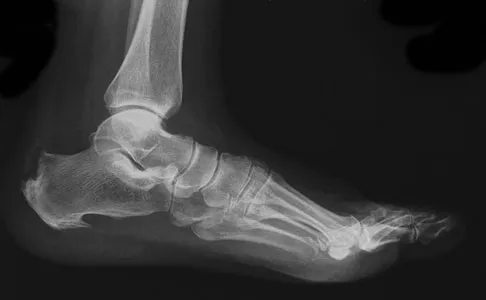

A 37-year-old woman has had intermittent paresthesias and numbness in the plantar foot for the past 6 months. She reports that the symptoms are worse with activity, and the paresthesias are beginning to awaken her at night. MRI scans are shown in Figures 6a and 6b. What is the most likely diagnosis?

Explanation

The symptoms are consistent with tarsal tunnel syndrome. Ganglion cysts are a well-known cause of tarsal tunnel syndrome. The MRI scans show a high intensity, well-circumscribed mass in the tarsal tunnel that is consistent with a fluid-filled cyst. Patients usually respond well to excision of the ganglion and resolution of the tarsal tunnel symptoms. The surrounding fat is a different signal intensity on the MRI scans, which rules out a lipoma. Synovial cell sarcoma has a heterogeneous appearance on an MRI scan. Metastatic tumors are most commonly found in the osseous structures of the foot, not the soft tissues. Rozbruch SR, Chang V, Bohne WH, et al: Ganglion cysts of the lower extremity: An analysis of 54 cases and review of the literature. Orthopedics 1998;21:141-148. Llauger J, Palmer J, Monill JM, et al: MR imaging of benign soft-tissue masses of the foot and ankle. Radiographics 1998;18:1481-1498.